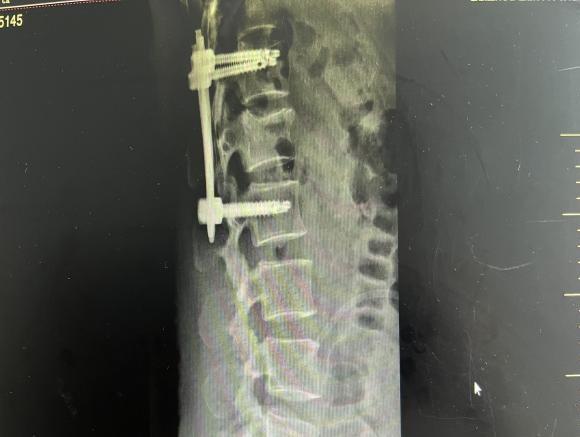

为提升区域内基层医疗机构糖尿病足诊疗服务能力、促进青年医师对糖尿病足的规范化诊治水平,遵义市第二城市医疗集团总院(贵州航天医院)圆满举办贵州省继续医学教育项目——胫骨横向骨搬移技术治疗糖尿病足专题研讨班。 贵州航天医院党委委员、副院长彭亮出席会议并致辞,遵义市第二城市医疗集团各成员单位,以及红花岗区、汇川区、绥阳县、桐梓县等多个区县的基层医疗机构骨干医师参加会议。 研讨班 本次研讨班以胫骨横向骨搬移技术在糖尿病足治疗中的应用为核心主题,围绕糖尿病药物治疗与生活方式管理策略、围手术期血糖精准调控要点、胫骨横向骨搬移技术典型病例深度解析、糖尿病足的临床分型与个体化治疗方案制定等临床实践中的热点与难点展开深入探讨,通过专题授课、案例研讨、互动交流等多元化形式,为参会者搭建了理论与实践结合的学习平台。 此次研讨班不仅为区域内基层医院搭建了学术交流与经验共享的平台,更对推动糖尿病足预防、诊断与治疗的规范化、系统化发展起到了积极作用,有效助力青年医师更新专业知识体系、提升临床技能,为进一步保障区域内糖尿病足患者的健康奠定了坚实基础。 贵州航天医院骨科专家简介 陈明勇 骨一科主任,副主任医师 临床擅长:从事创伤骨科工作约20年,对骨缺损、骨不连、骨肿瘤、肢体畸形等的肢体矫形重建及功能重建,慢性化脓性骨髓炎的根治治疗、糖尿病足的保肢治疗、快速康复理念(ERAS)下的老年骨折的诊治,四肢复杂骨折的诊治,四肢骨折等微创手术治疗具有丰富的临床经验。 2004年毕业于遵义医学院临床专业,曾在中国人民解放军总医院、广西医科大学第一附属医院、上海第六人民医院骨科进修。中国中西医结合学会骨伤科专业委员会横向骨搬移治疗糖尿病足及微血管网再生学组首届委员,遵义市医学会创伤分会常务委员。 瞿 晖 骨科党支部书记,骨二科主任,副主任医师 临床擅长:对骨科的常见病、关节外科、脊柱外科及运动医学疾病的诊治具有丰富的临床经验,熟练掌握骨科手术操作技术。 毕业于遵义医学院临床医学系,2005年前往广州中山大学第一附院骨显微医学部进修学习,2011年前往成都华西医院进修学习,并多次在省内外学习骨科相关知识,是中华医学会骨科分会会员。 赵小锋 中共党员,骨二科副主任,副主任医师 临床擅长:从事骨科临床工作11年,对骨科常见病、多发病诊疗有较为丰富的临床经验,擅长脊柱相关疾病诊断及治疗,尤其是颈、腰、腿疼痛疾病诊断及治疗,擅长胸腰椎骨折微创经皮穿刺内固定术、经皮穿刺椎体成形术、经皮穿刺脊柱内镜下腰椎间盘摘除术、单纯开创腰椎间盘摘除术、腰椎滑脱复位椎间植骨椎融合内固定术、腰椎管狭窄减压融合内固定术及人工髋、膝关节置换术等。 2012年毕业于遵义医学院外科学专业硕士研究生,2019年参加“遵义市115医学人才精英计划”于上海交通大学第一附属医院培训学习,2023年于北京大学第三人民医院脊柱外科进修学习,曾获得遵义市优秀医师荣誉称号。 遵义市手外科第一届委员,遵义市医学会创伤分会第一届委员,遵义市医学会创伤分会第二届委员,贵州省康复医学会第三届脊柱脊髓专业会委员,遵义市医学会烧伤与整形外科学分会委员,发表论文5篇,其中国家级核心期刊1篇,SCI论文1篇,主持市级课题1项并结题,参与市级课题2项。 赵兴东 骨科主任医师 临床擅长:擅长骨科的常见病及各种创伤、四肢骨折创伤修复、骨感染、手足疾病的诊治和手足体表畸形的矫形整复,熟练掌握骨科四肢骨病及创伤的手术操作技术,尤其在四肢关节复杂性损伤、手足外伤、组织缺损创面、难治创面的皮瓣修复方面及平足、高弓足矫形方面及四肢慢性疼痛诊治、康复方面具有丰富的临床经验。 硕士研究生,毕业于遵义医学院临床外科系,2015年前往山东省立医院手足外科进修学习;遵义市医学分会创伤分会第一、二届委员,遵义市手外科医学会第二委届员会常务委员;在省级及省级以上期刊发表文章9篇,参编著作2部,参与主持并完成市级课题1项,参与市级课题2项、省级课题1项。 张艳金 中共党员,骨科副主任医师 临床擅长:从事骨外科工作16年,对复合伤、多发伤的救治、四肢骨干骨折、关节周围骨折、骨肿瘤、骨髓炎等诊治具有丰富的临床经验。 中共党员,硕士研究生,2006年本科毕业于山西医科大学第二临床医学院,2011年研究生毕业于北京军区总医院;在“老年COPD患者合并髋部骨折的诊治”国际合作课题组研究两年,在老年髋部骨折的诊治方面具有丰富的经验,并发表论文6篇;主持遵义市级课题1项,承担遵义医科大学的临床教学工作,获得遵义医科大学优秀带教老师荣誉。编撰有《骨科疾病诊疗精粹》一书,开展2项新技术,编撰地方规范《务川自治县创伤骨科常见疾病诊疗规范》一书。 张俊凯 骨科副主任医师 临床擅长:从事骨科临床工作28年,对创伤骨折、骨感染、骨缺损、骨不连等外科诊治,四肢骨折的微创手术治疗,四肢复杂骨折(如关节内粉碎性骨折、多发骨折等)的损伤控制及手术治疗等具有丰富的临床经验。 1995年毕业于遵义医学院临床专业,2009年前往复旦大学附属医院骨科进修1年。 卢懿明 中共党员,骨科副主任医师 临床擅长:从事骨科工作18年,对创伤骨折、四肢骨折的微创手术治疗、四肢复杂骨折(如关节内粉碎性骨折、多发骨折等)的损伤控制及手术治疗,尤其是髋部骨折的PFNA等微创技术,踝关节骨折、膝关节周围骨折的Mipo微创技术等具有丰富的临床经验,开展了4项新技术,发明6项新型专利技术。 2005年毕业于遵义医学院临床专业,2017年,前往南方医科大学第三附属医院骨科进修半年,回院后运用Mipo技术对骨干骨折及干骺端骨折的治疗技术,同时积极开展骨盆骨折、髋臼骨折腹直肌外侧切口的应用;发表了多篇专业论文,经常参与省内外学术交流会授课,获得医院荣誉称号多个。 邬夏荣 骨科副主任医师 临床擅长:从事骨科工作16年,对四肢复杂骨折、骨肿瘤的诊治,尤其是足踝创伤、慢性踝关节损伤、平足症等诊疗具有丰富的临床经验。 2006年毕业于遵义医科大学临床医学专业,曾在陆军军医大学西南医院进修学习,发表多篇骨科学术论文。 余德怀 中共党员,骨科副主任医师 临床擅长:从事骨科工作10余年,对运动医学、骨关节、脊柱外科常见病、多发病的诊治具有丰富的临床经验。 硕士研究生,2011年毕业于遵义医学院临床医学专业,曾前往遵义医科大学附属医院运动医学专业进修学习;是贵州省医学会运动医学分会青年委员,西部关节镜联盟委员;发表多篇骨科学术论文。 冯 乾 骨科副主任医师 临床擅长:从事骨科工作近20年,熟练掌握骨科多发病及常见病的诊治,尤其对脊柱退变性疾病的诊断及治疗具有丰富的临床经验,主要研究脊柱微创相关治疗方式,能熟练开展椎间孔镜及UBE。 曾前往北京大学第三医院进修学习疼痛及椎间孔镜、首都医科大学友谊医院专业进修脊柱内镜;是贵州省康复医学会第三届脊柱脊髓专业委员会委员;发明专利3项、发表脊柱外科专业论文多篇。 贵州航天医院骨科简介 基本情况 贵州航天医院(原3417医院)骨科组建于1968年,前身是以创伤和断肢(断指)再植闻名于世的上海市第六人民医院骨科,中国断肢(断指)再植的奠基者、中科院院士陈仲伟等专家莅临科室指导医疗和教学,并在70年代开展了贵州省首例断肢(断指)再植手术。组建50余年来,诊治患者已逾百万,挽救了无数的伤病员,成为了保障遵义地区人民群众健康的重要支撑。 经过几代人的不懈努力,今天的骨科,已由创伤骨科发展至骨病、骨肿瘤、骨结核等领域,现有脊柱外科、关节外科、四肢创伤、手足外科四个亚专科,成为了集医疗、教学、科研于一体的综合学科,是贵州省临床重点专科、遵义市临床重点专科、遵义市骨科临床医学中心、遵义市基层骨科专科联盟理事长单位。 科室目前开放床位110张,共有医护人员50余人,副高级以上专家18人,硕士研究生15人。拥有一流骨科医疗设备多台,每年不定期选派优秀技术骨干到全国各大知名医学院校进修、学习、参观、交流,并邀请国内、国外知名专家教授来院进行交流、指导,通过不断引进国内外先进的诊疗技术,科室医疗技术水平稳步提升,为广大人民群众提供了优质的医疗服务。 专科特色 骨一科 (一)骨缺损、骨不连的肢体与功能重建 胫骨横向骨搬移技术治疗糖尿病足: (二)慢性骨髓炎的根治治疗 (三)肢体缺血性疾病如糖尿病足、脉管炎的保肢治疗 (四)皮瓣修复 (五)复杂创伤的治疗 (六)老年髋部骨折及小儿骨折快速手术 老年髋部骨折: 骨二科 (一)胸腰椎骨折微创经皮椎弓根螺钉固定术 (二)老年性骨质疏松性患者腰椎滑脱脊柱内固定术(骨水泥螺钉) (三)V形双通道脊柱内镜技术(VBE)腰椎融合术治疗腰椎退行性疾病 (四)老年性骨质疏松性骨折(PVP/PKP)术 (五)人工髋关节置换术 (六)双侧股骨头坏死人工全髋关节置换 (七)右侧全髋置换术后假体周围骨折翻修 (八)人工膝关节置换术 (九)人工膝关节假体松动翻修 (十)关节镜技术 传统手术切口 关节镜技术切口 诊疗范围 骨一科 1.四肢创伤、矫形。 2.手、足踝外科。 骨二科 End